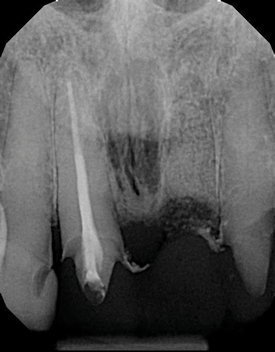

(11.) A pathosis apical to the maxillary central incisors was initially not diagnosed after evaluating the periapical film; however, the CBCT image revealed its presence. Only using the CBCT image could it be determined that the lesion was not odontogenic in origin and that it did not involve the nasopalatine foramen. This diagnosis was supported by a referral to an oral and maxillofacial radiologist.

Figure 11

(12.) A pathosis apical to the maxillary central incisors was initially not diagnosed after evaluating the periapical film; however, the CBCT image revealed its presence. Only using the CBCT image could it be determined that the lesion was not odontogenic in origin and that it did not involve the nasopalatine foramen. This diagnosis was supported by a referral to an oral and maxillofacial radiologist.

Figure 12

Are most or all dentists qualified to read CBCT images? Although the technology can be intimidating to clinicians who are not experienced in its use, the truth of the matter is that it is easier to identify structures and pathoses in CBCT images than in any 2D radiograph. This is made clear by the ability of patients to see and understand the images presented to them without receiving any formal training whatsoever. Because all dentists are trained in radiology, they can easily read a radiographic image created by a cone beam. The real issue for clinicians involves mastery of the software that their particular CBCT unit uses so that they can manipulate the images and best visualize the area in question.9 To this end, the education and training provided by the manufacturers of CBCT units can be very helpful to clinicians before they are able to gain experience through multiple evaluations of images (Figure 11 and Figure 12).

Dentists who become experienced in evaluating CBCT images become more advanced in their knowledge of anatomy as well as their familiarity with variations in normal structures. As they experience more findings, they also learn to better differentiate between normal and pathological scenarios and recognize pathoses in greater depth and detail. If dentists see something that they are not familiar with or comfortable identifying, they can refer the patient to an oral and maxillofacial radiologist.